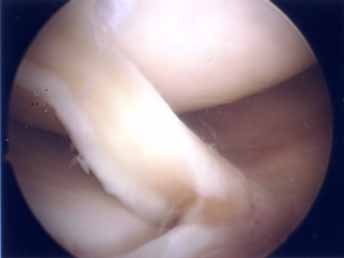

第3段階軟骨形成術

第2段階からさらに進行するとより広範囲の軟骨障害になりさらに軟骨の障害も深くなります。この段階ではドリリング手術を加えることが多くなります。第3段階ではまだ人工関節は適応はありませんのでできるだけ軟骨形成術をして膝の痛みを軽減し少しでも長く自分の膝で歩けるようにが目的です。本手術の結果は平均60~80点で患者の満足度は比較的高いので手術は安心下さい。